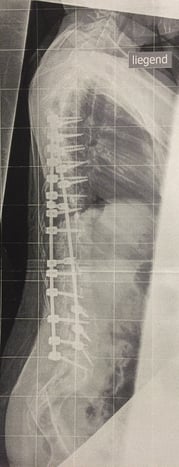

Es werden Fotos und Röntgenaufnahmen gezeigt.

Es folgen eine lange Reihe von sehr eindrucksvollen Fotos, Röntgenbilder, Vorher-Nachher-Bilder.

Ausgangsituation

nach Korrektur

von der Seite gesehen